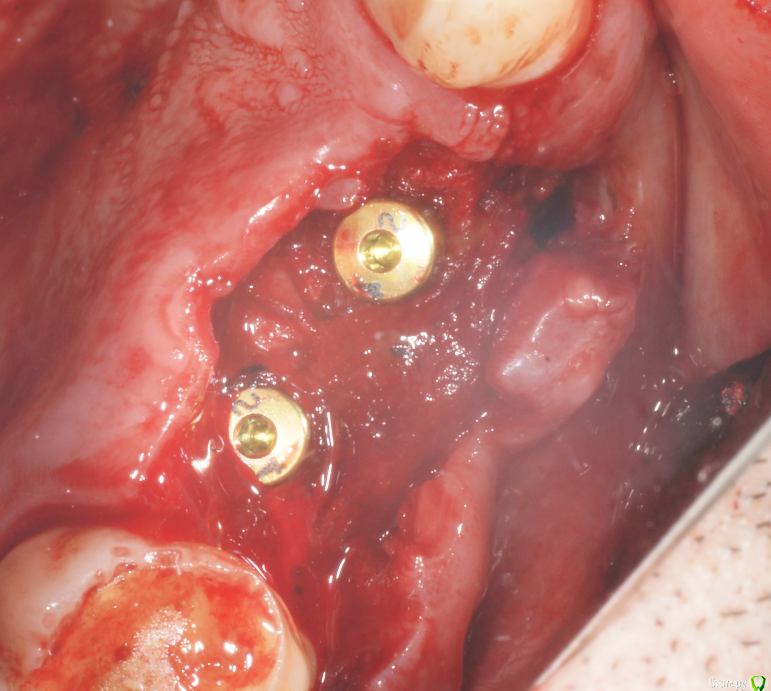

В начале планировал три имплантата, между зубами - 18,5 мм, в притык. Когда делал анестезию посмотрел наконец-то в рот (не смейтесь, внимательно посмотрел) - подумал, что моляр и два премоляра ортопед может не всунуть. Короче, передумал и решил ставить два и если че - пусть мостик или консоль делает.

post-39476-0-20587600-1491829543_thumb.pngpost-39476-0-72650200-1491829557_thumb.pngpost-39476-0-01103300-1491829573_thumb.pngpost-39476-0-55620900-1491829587_thumb.png

За качество некоторых фото прошу прощения, что мог делал сам, но в гуще событий доверил камеру второму ассистенту. Уговорить человека не прожимать спуск без задержки на автофокус не удалось, как и заставить приблизиться ближе чем на метр. Радует что когда закупался то выбрал макросотку - на 60мм которую мне предлагали вообще нифига не видно было бы.